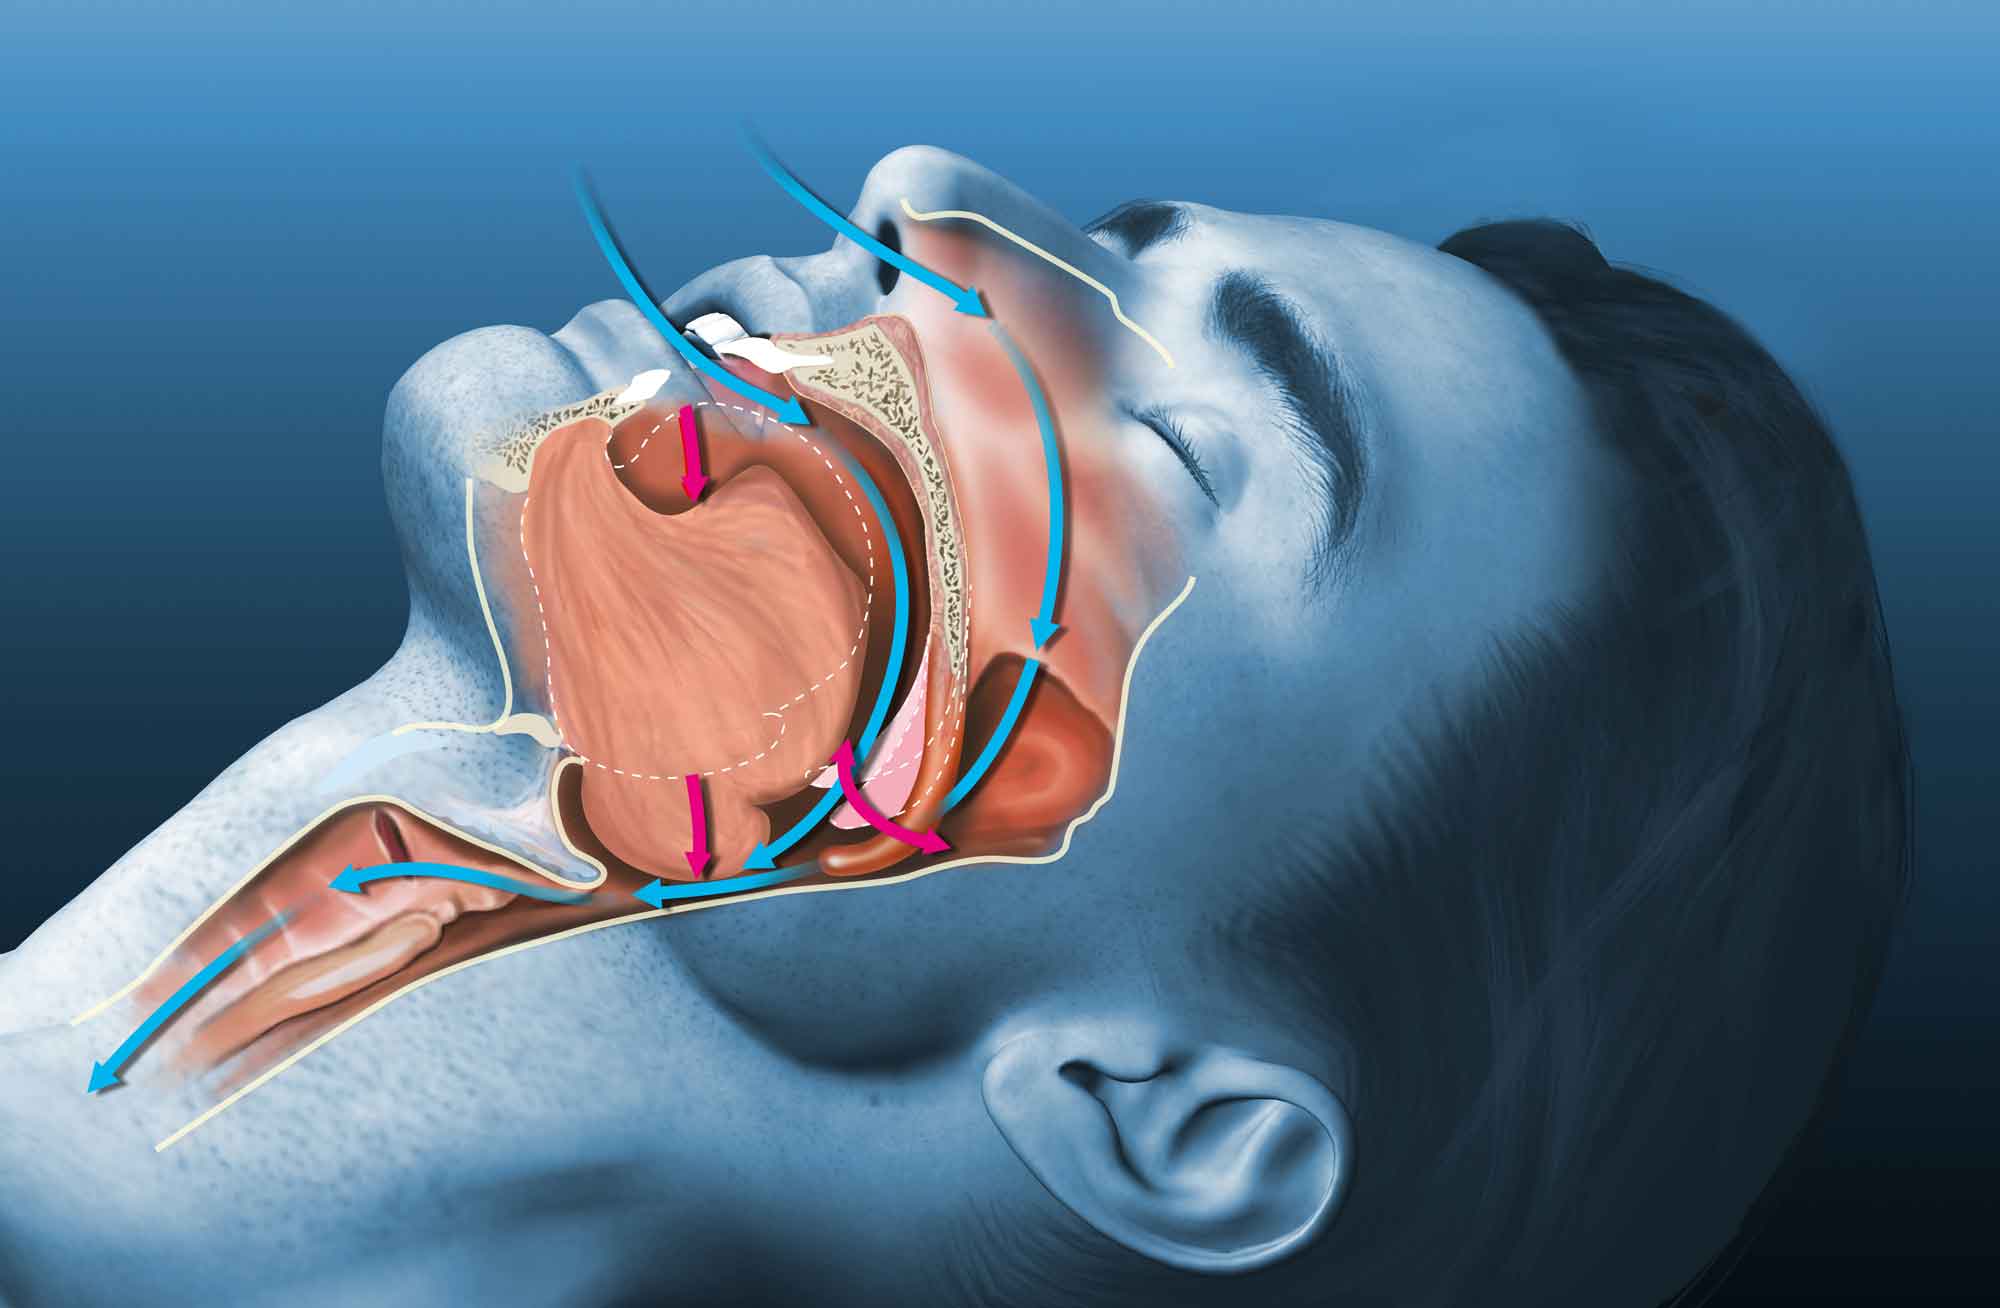

What’s keeping you up at night? Bouts of snoring and constant waking can be signs of sleep apnea. And tooth grinding or sore jaws can be indicators of TMJ disorder. No matter why you can’t seem to get rest, talk to our oral surgeons in Flower Mound and Denton, TX. We can introduce you to customized, high-tech non-invasive, minimally invasive, and surgical sleep apnea and TMJ treatment solutions.

Like his colleague Dr. Vickers, Dr. Anver received both his DDS and MD degrees to set himself apart from other dental practitioners. When working with patients, he concentrates on making their experiences as comfortable and successful as possible. Dr. Anver’s professional interests include performing all types of tooth extractions, administering IV anesthesia, and placing dental implants. He’s also interested in helping individuals address TMJ disorder and related conditions.